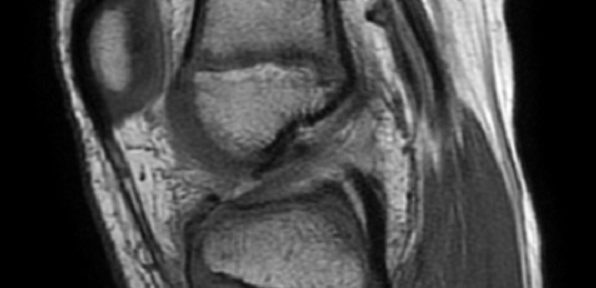

On Nov.30, 2021, he injured his left knee by his own movement during playing soccer. On the same day, he was taken to the hospital and scanned through the x-ray. On Dec.11, 2021, he was taken through the MRI scanning, and the diagnosis was:

ACL Tear

Suspected Avulsion Fracture of tibial spine

His doctor said that he was too young to have the ACL reconstruction as there is a high risk of interfering the bone growth. On Jan.18, he and his family visited Jun Matsumoto and started the Evo-Devo EX. for natural healing of the ACL tear. The Lackman’s test was positive. He continued the Evo-Devo EX. through the face-to-face and online sessions. The next MRI was taken on Mar.30.

Even though the MRI pictures don’t show the clear continuity of the ACL, the Lackman’s test was negative at that time. After continuing the Evo-Devo EX. furthermore, he took the third MRI on Aug.17.

The MRI indicates:

Even though the T1 pictures don’t show the clear appearance of the natural healing, the T2 picture(the first one pf 08/17) shows the continuity of the ACL.

Due to the poor resolution of the 1.5T MRI, it is difficult to have the exact diagnosis from these MRI. However, from the results of MRI and Lachman’s test, it can be inferred that the ACL healed spontaneously. Around 10 months from the injury, he already recovered the full range of motion of the knee, and started attending the physical education class at school. After one year from the injury, he plans to return to playing soccer.